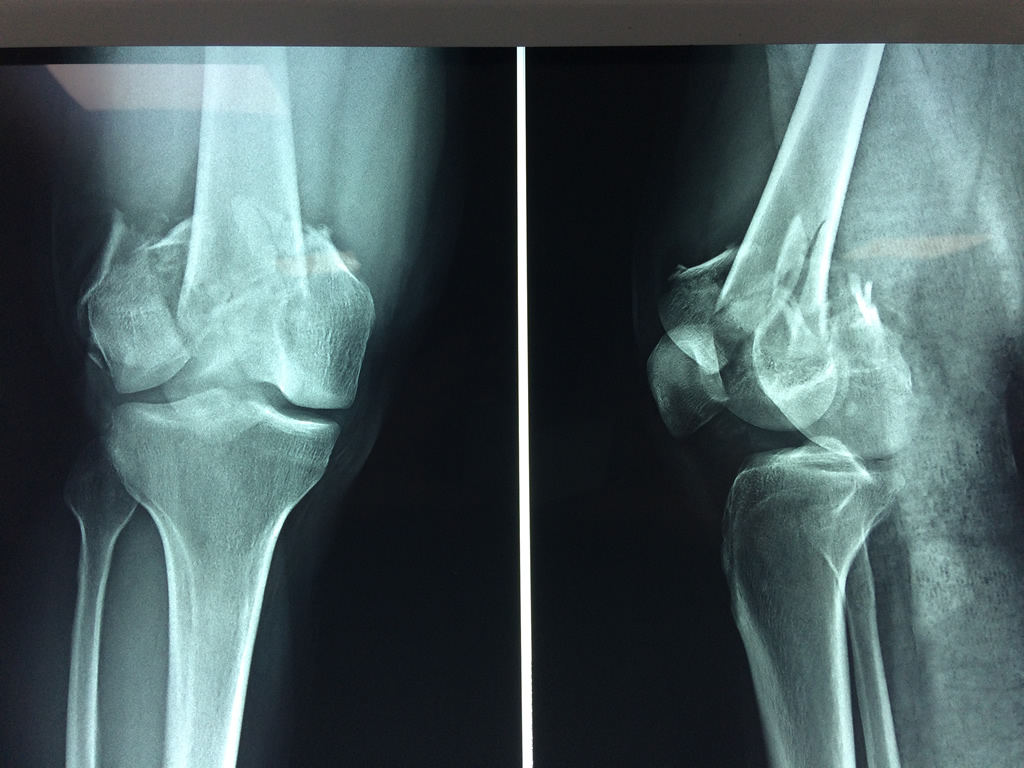

Cirugía de Fémur - Fémur

El fémur es el hueso del muslo, el segundo segmento del miembro inferior. Es el hueso más largo, fuerte y voluminoso del cuerpo humano.